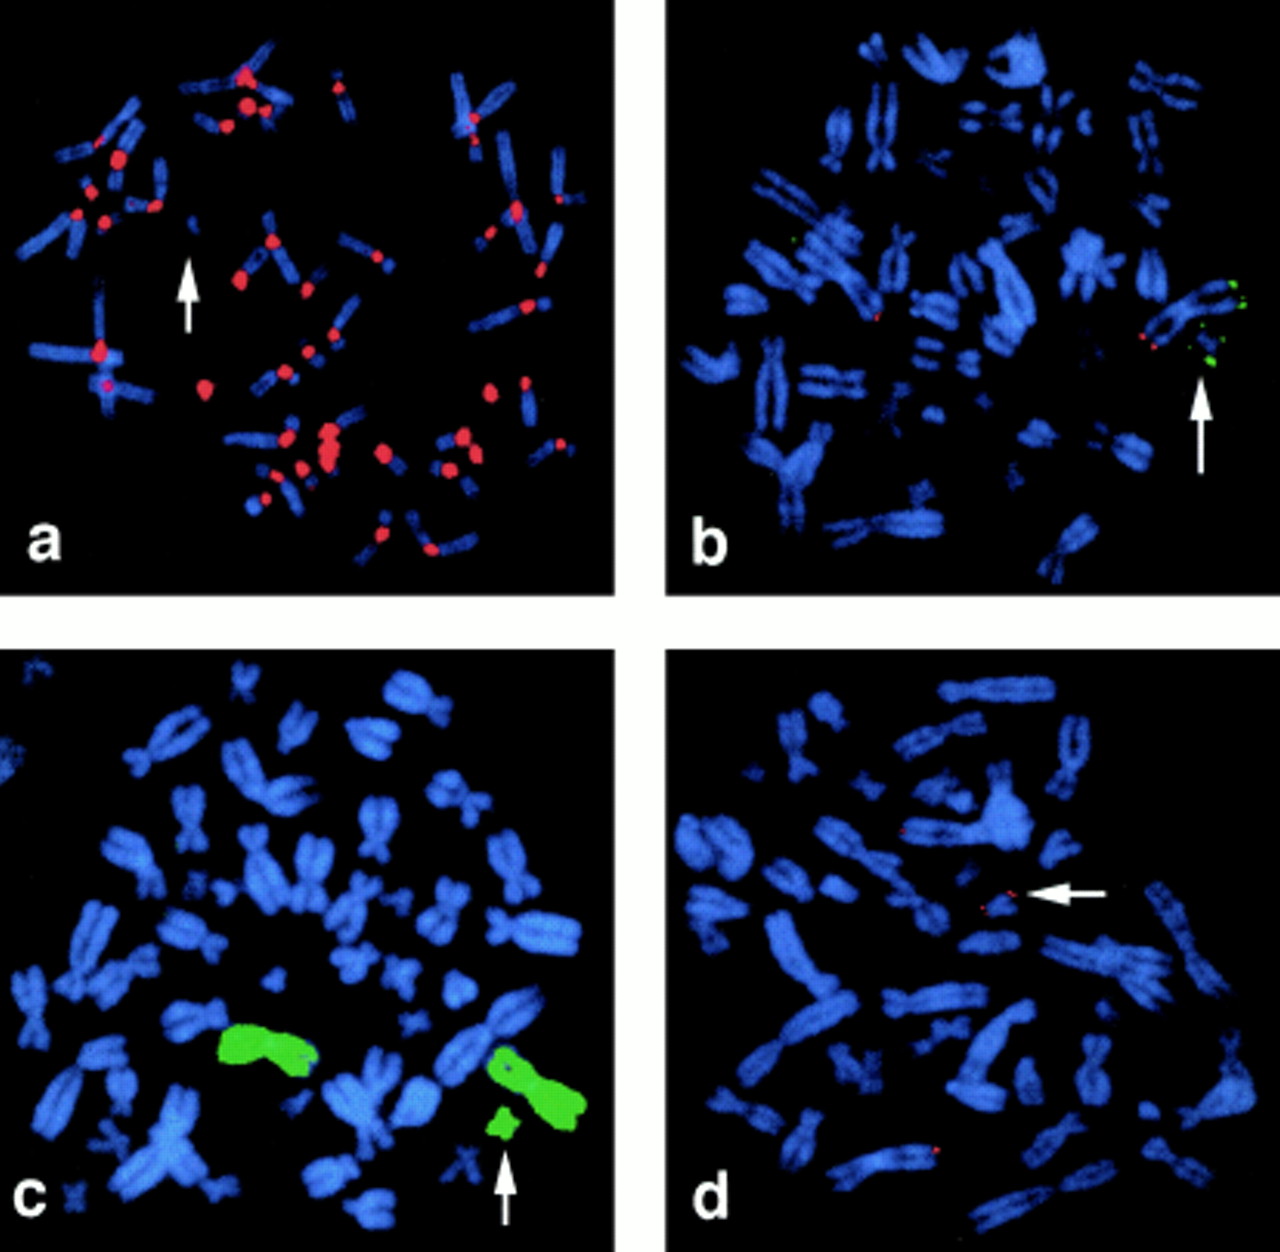

An analphoid supernumerary marker chromosome derived from chromosome 3 …